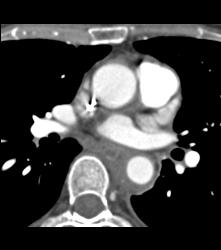

Multiple Incidental Pulmonary Emboli (PEs) in Patient With Pancreatic Cancer